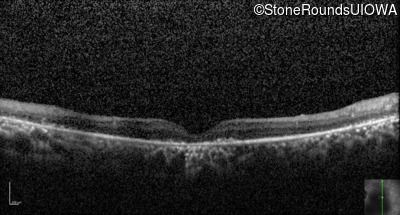

Optical Coherence Tomography - Left - 20/500 sc

Exemplar / OCT Stack

OCT Stack